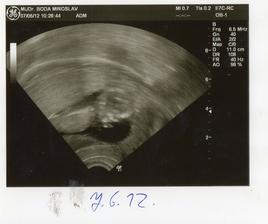

Nas anjelik Alex

Zatial este schovany v brusku ale uz coskoro sa z neho potesime aj nazivo 🙂) Lubime nasho Alexa uz od sameho zaciatku 🙂